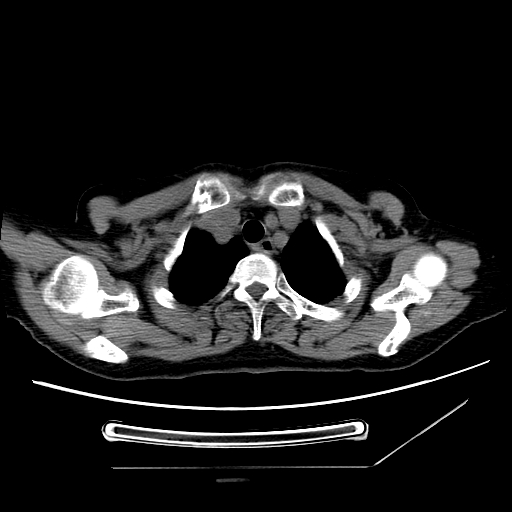

1、左肺中央型肺癌并双肺弥漫性转移   2、双肺部感染    3、肺大泡     4、左侧胸腔积液

双侧肺弥漫性病变,可见“空泡征”及“蜂窝征”,考虑肺泡癌可能性大,左侧胸腔积液,考虑胸膜受累可能!